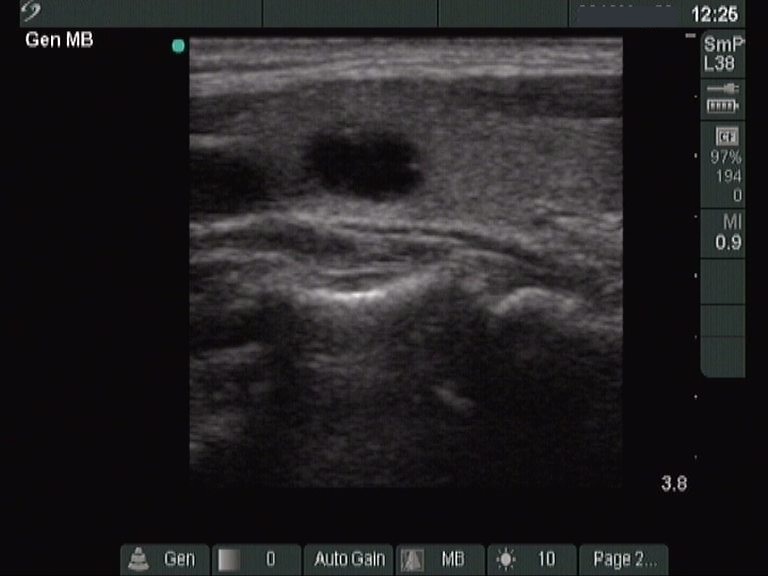

This is an almost completely cystic lesion, however it does not meet the criteria of a pure cyst. The wall thickening (yellow arrows) is ambiguous but there is a tiny solid-appearing area in the dorsal wall (red arrows). In systems which do not use the term 'almost completely cystic lesion', this nodule should be categorized as a peripheral-type cyst.